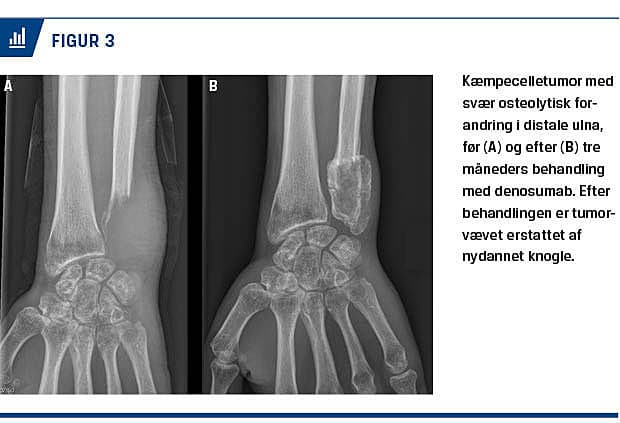

Sørensen et al [19] undersøgte fem patienter og fandt en kraftig og relativt uregelmæssig knoglenydannelse af tumorvævet efter 3-8 måneders Dmab-behandling (Figur 3). Hos tre af patienterne fandt man ved DXA-skanning en 37-44% stigning i BMD i tumorområdet 3-8 måneder efter påbegyndelse af Dmab-behandling.

handlingen bestod vævsprøverne af en celletæt blanding af RANKL-positive stromaceller, et højt niveau af RANK-positive kæmpeceller og sparsomme fokale områder med nydannet knogle. Efter Dmab-behandlingen var mængden af kæmpeceller som anført reduceret > 90%, og man observerede også en reduktion i mængden af stromaceller. I 65% af prøverne blev stromacellerne erstattet af fibroossøst væv og/eller nydannet knogle. Tilsvarende fandt Sørensen et al [19], at tumorvævet var erstattet af cellefattigt fibrøst væv uden påviselige kæmpeceller (Figur 4).